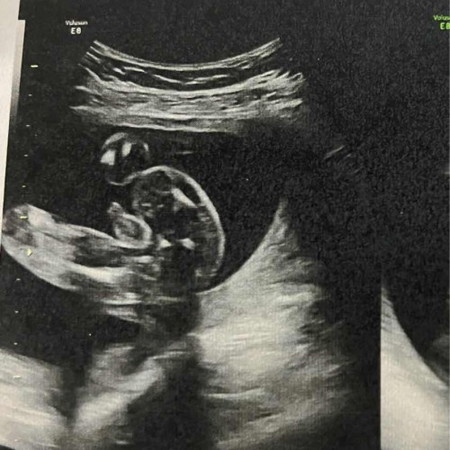

ตอนอัลตร้าซาวด์คุณหมอบอกว่าน้องเป็นเพศชาย น้องจะมีสิทธิ์เป็นเพศหญิงไหมคะ หรือเพศชาย 100%

คนแรกเราผู้ชาย จะเห็นชัดแบบนี้เลยค่ะ ไม่ใช่สายรกแน่นอน คนสองเราเป็นผู้หญิง ซาวด์หว่างขาน้องจะเป็นกลีบ ไม่ยื่นมาแบบนี้ค่ะ

ของน้องที่ทำงานเราก็ทรงแบบนี้นะ โด่ๆเป็นทรงจู๋แบบนี้เลย หมอนัดซาวอีกรอบเป็น ผญ. ไอ้ที่โด่คือสายสะดือ 🙄😆

มีโอกาสเป็นผู้ชายค่ะ ถ้าสิ่งที่หมอเห็นเป็นสายสะดือ ไม่ใช่อวัยวะเพศชาย แต่ดูจากรูปแล้วเป็นผู้ชายค่ะ

บ้านนี้ซาวด์รอบแรกโชวแบบนี้เลยค่ะ พอรอบ2เห็นทั้งไข่ด้วย..ชายแน่ค่ะแม่ไม่เปลี่ยนแน่ค่ะ☺